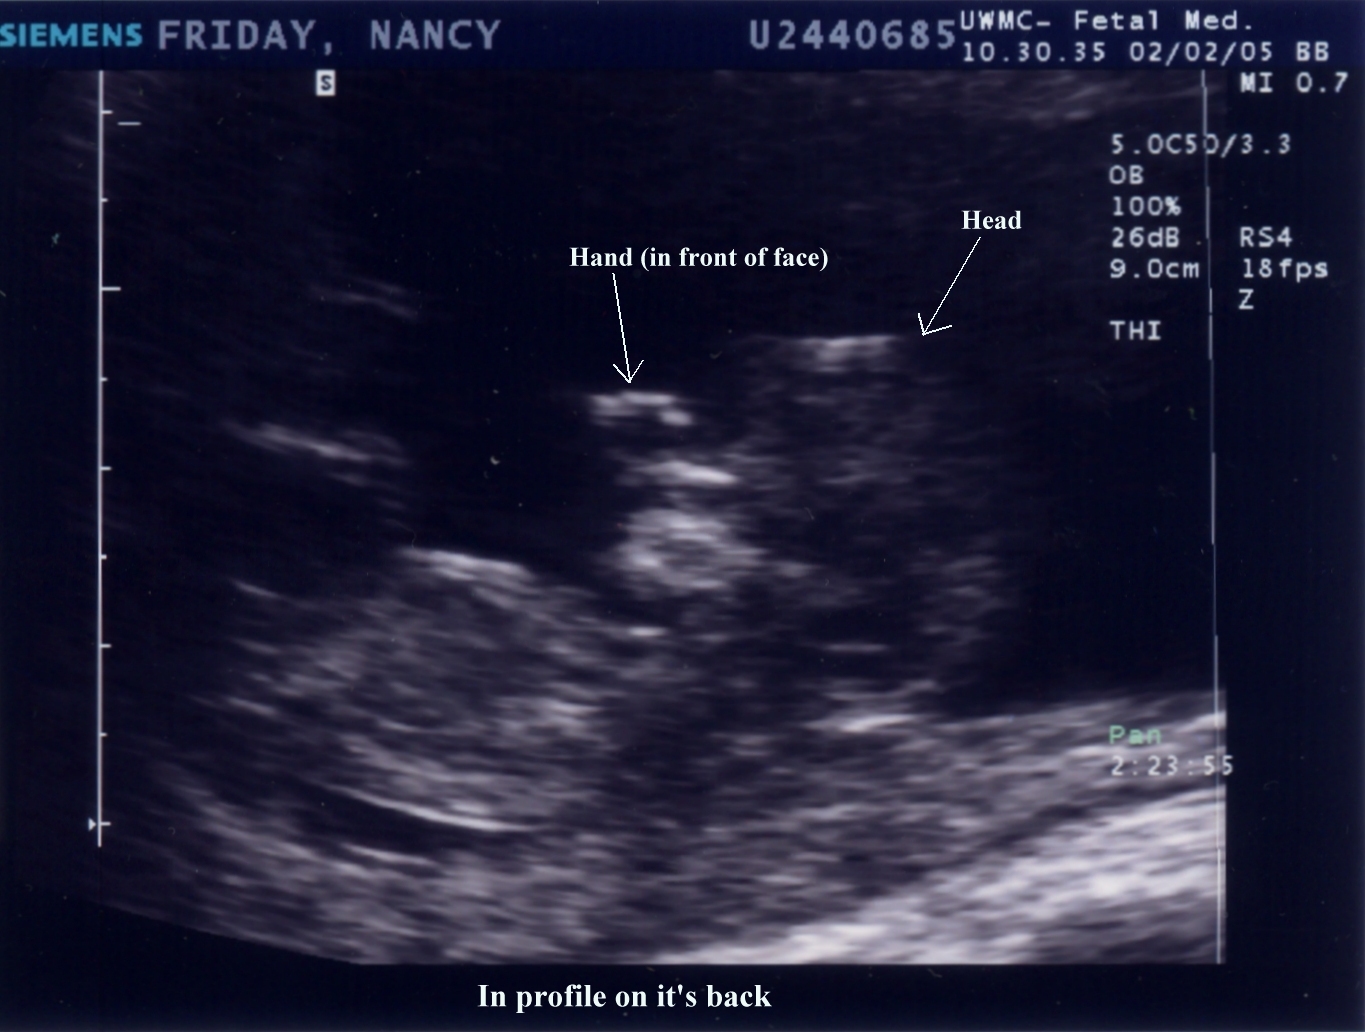

February 2, 2005 - 11.5 weeks (9.5 weeks from conception)  |